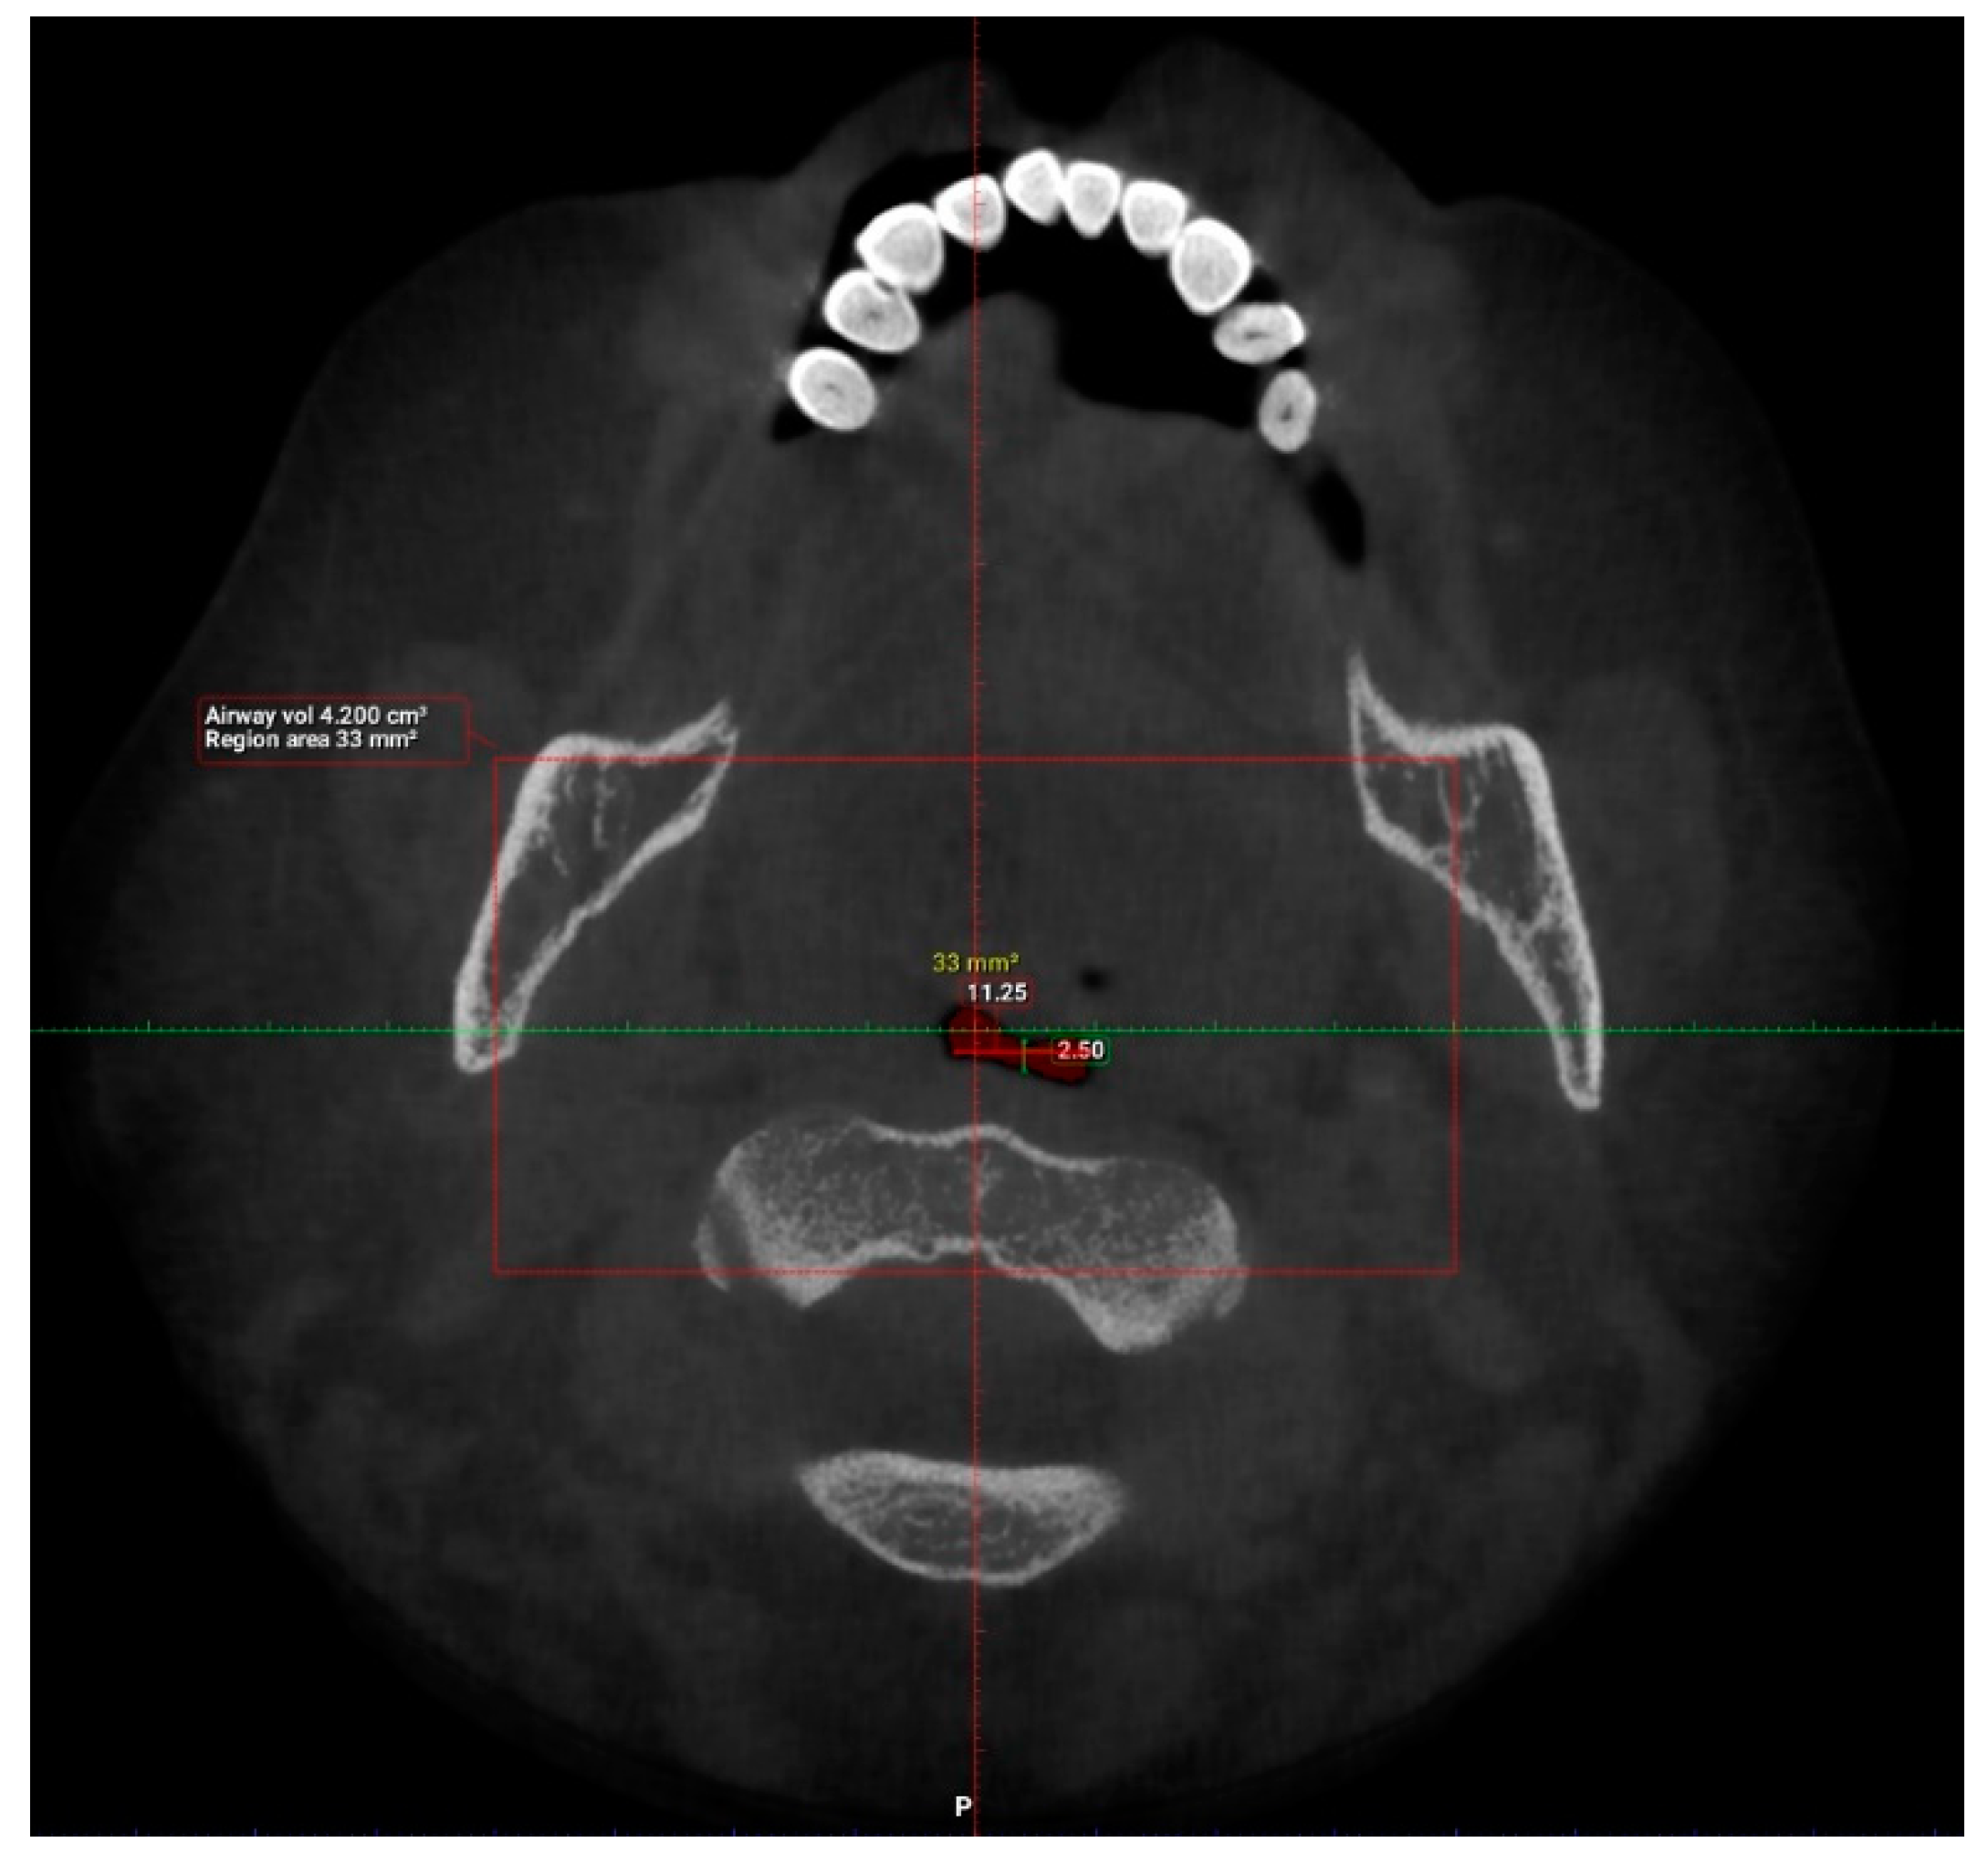

| N | Minimum | Maximum | Mean | Std. Deviation | |

| Length (mm) | 101 | 29.93 | 55.75 | 42.63 | 6.24 |

| Total volume (cm3) | 101 | 94.58 | 173.45 | 131.67 | 17.91 |

| Average volume (cm3) | 101 | 3.34 | 32.09 | 11.10 | 5.21 |

| Antero-posterior (mm) | 101 | 1.00 | 14.50 | 6.44 | 3.19 |

| Width (mm) | 101 | 8.00 | 37.00 | 21.69 | 6.54 |

| Valid N (listwise) | 101 |